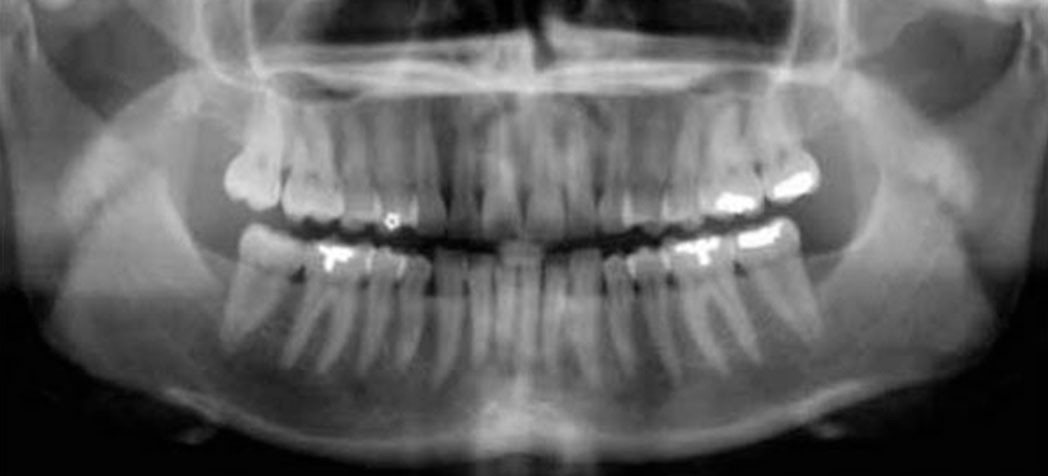

Панорама (ортопантомограмма, ОПТГ, панорамный снимок челюстей) – это обзорный круговой снимок зубов, при котором видна вся челюсть, развернутая в двухмерной плоскости. Она может быть цифровой и пленочной.

Панорамный снимок (или ортопантомограмма) – это плоское двухмерное изображение челюстей, зубов, гайморовых пазух и даже височно-нижнечелюстного сустава. Поскольку поверхность челюстей изогнутая, на плоской рентгеновской плёнке снимок отображается неравномерно увеличенным в боковых и передних отделах челюстей – то есть слегка деформированым.

Панорамный снимок челюсти позволяет стоматологу получить изображение сразу всех зубов, включая верхнечелюстные суставы.

На рентгене отображаются зубные каналы, корни, костная ткань, пломбы и импланты.